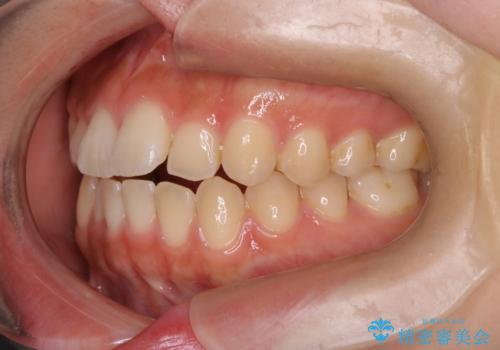

- 前歯の叢生を主訴に来院されました。非抜歯でインビザラインで治療をしました。

叢生はIPRをし、並べました。この患者様はオープンバイトだったため歯を並べる過程でかみ合わせも治しました。